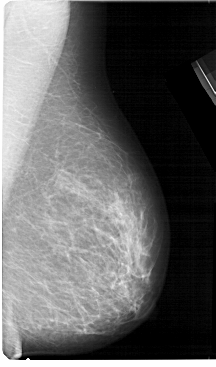

A_1323_1.LEFT_CC

LEFT_CC LINES 5296 PIXELS_PER_LINE 2896 BITS_PER_PIXEL 12 RESOLUTION 43.5 OVERLAY